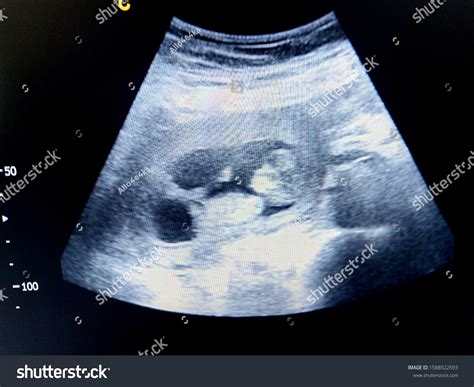

11 Week Ultrasound Pictures

Pregnancy is an exciting journey filled with milestones, and one of the most anticipated moments is the 11-week ultrasound. This scan provides valuable insights into the baby's development and offers parents their first detailed glimpse of their growing child. Understanding what to expect from 11 week ultrasound pictures can help alleviate anxiety and build excitement for this significant event.

Interpreting 11 Week Ultrasound Pictures

11 week ultrasound pictures can reveal a wealth of information about the baby's development. Here are some key features to look for:

• Crown-Rump Length (CRL): This measurement is taken from the top of the baby's head to the bottom of the buttocks. It helps determine the baby's gestational age and overall growth.

• Heartbeat: The baby's heart should be beating strongly and steadily. The heartbeat is a crucial indicator of the baby's health.

• Amniotic Fluid: The amount of amniotic fluid surrounding the baby is important. Too much or too little fluid can indicate potential issues.

• Placenta Location: The placenta's position is checked to ensure it is not covering the cervix, which could lead to complications later in the pregnancy.